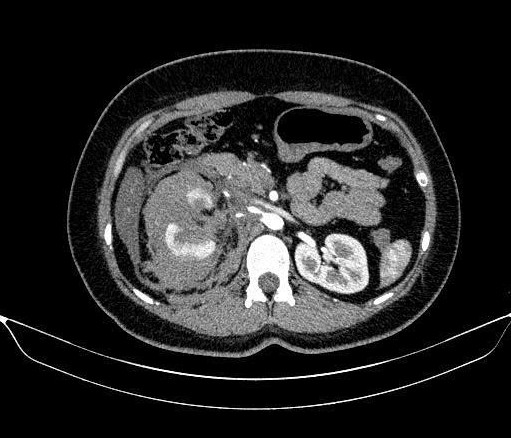

Hình ảnh chụp CT bụng của bệnh nhân. Ảnh: BVCC

Kết quả cho thấy bệnh nhân bị vỡ thận phải độ IV theo phân loại AAST 2018 là mức độ tổn thương nặng, nguy cơ cao phải cắt thận nếu xử trí không kịp thời.

Ca can thiệp do ThS.BSCKII Lê Hồng Kỳ, Trưởng khoa Chẩn đoán hình ảnh & Y học hạt nhân, trực tiếp thực hiện. Chụp động mạch thận phải ghi nhận tình trạng thoát thuốc từ các nhánh động mạch cực dưới. Ê kíp tiến hành can thiệp siêu chọn lọc bằng microcatheter, nút mạch bằng hỗn dịch Histoacryl – Lipiodol kết hợp Spongel.

Chụp kiểm tra sau can thiệp cho thấy các nhánh mạch tổn thương được tắc hoàn toàn, phần nhu mô thận còn lại được bảo tồn tốt. Thủ thuật diễn ra an toàn, không ghi nhận biến chứng trong và ngay sau can thiệp.